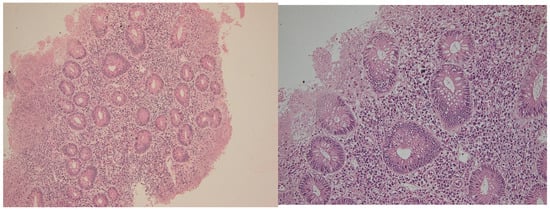

2.1. Histological Disease Activity

2.2. Distribution of T Lymphocyte Subsets

2.2.1. Cd4+ Lymphocytes

2.2.2. CD8+ Lymphocytes

4.7. Immunohistochemical Analysis